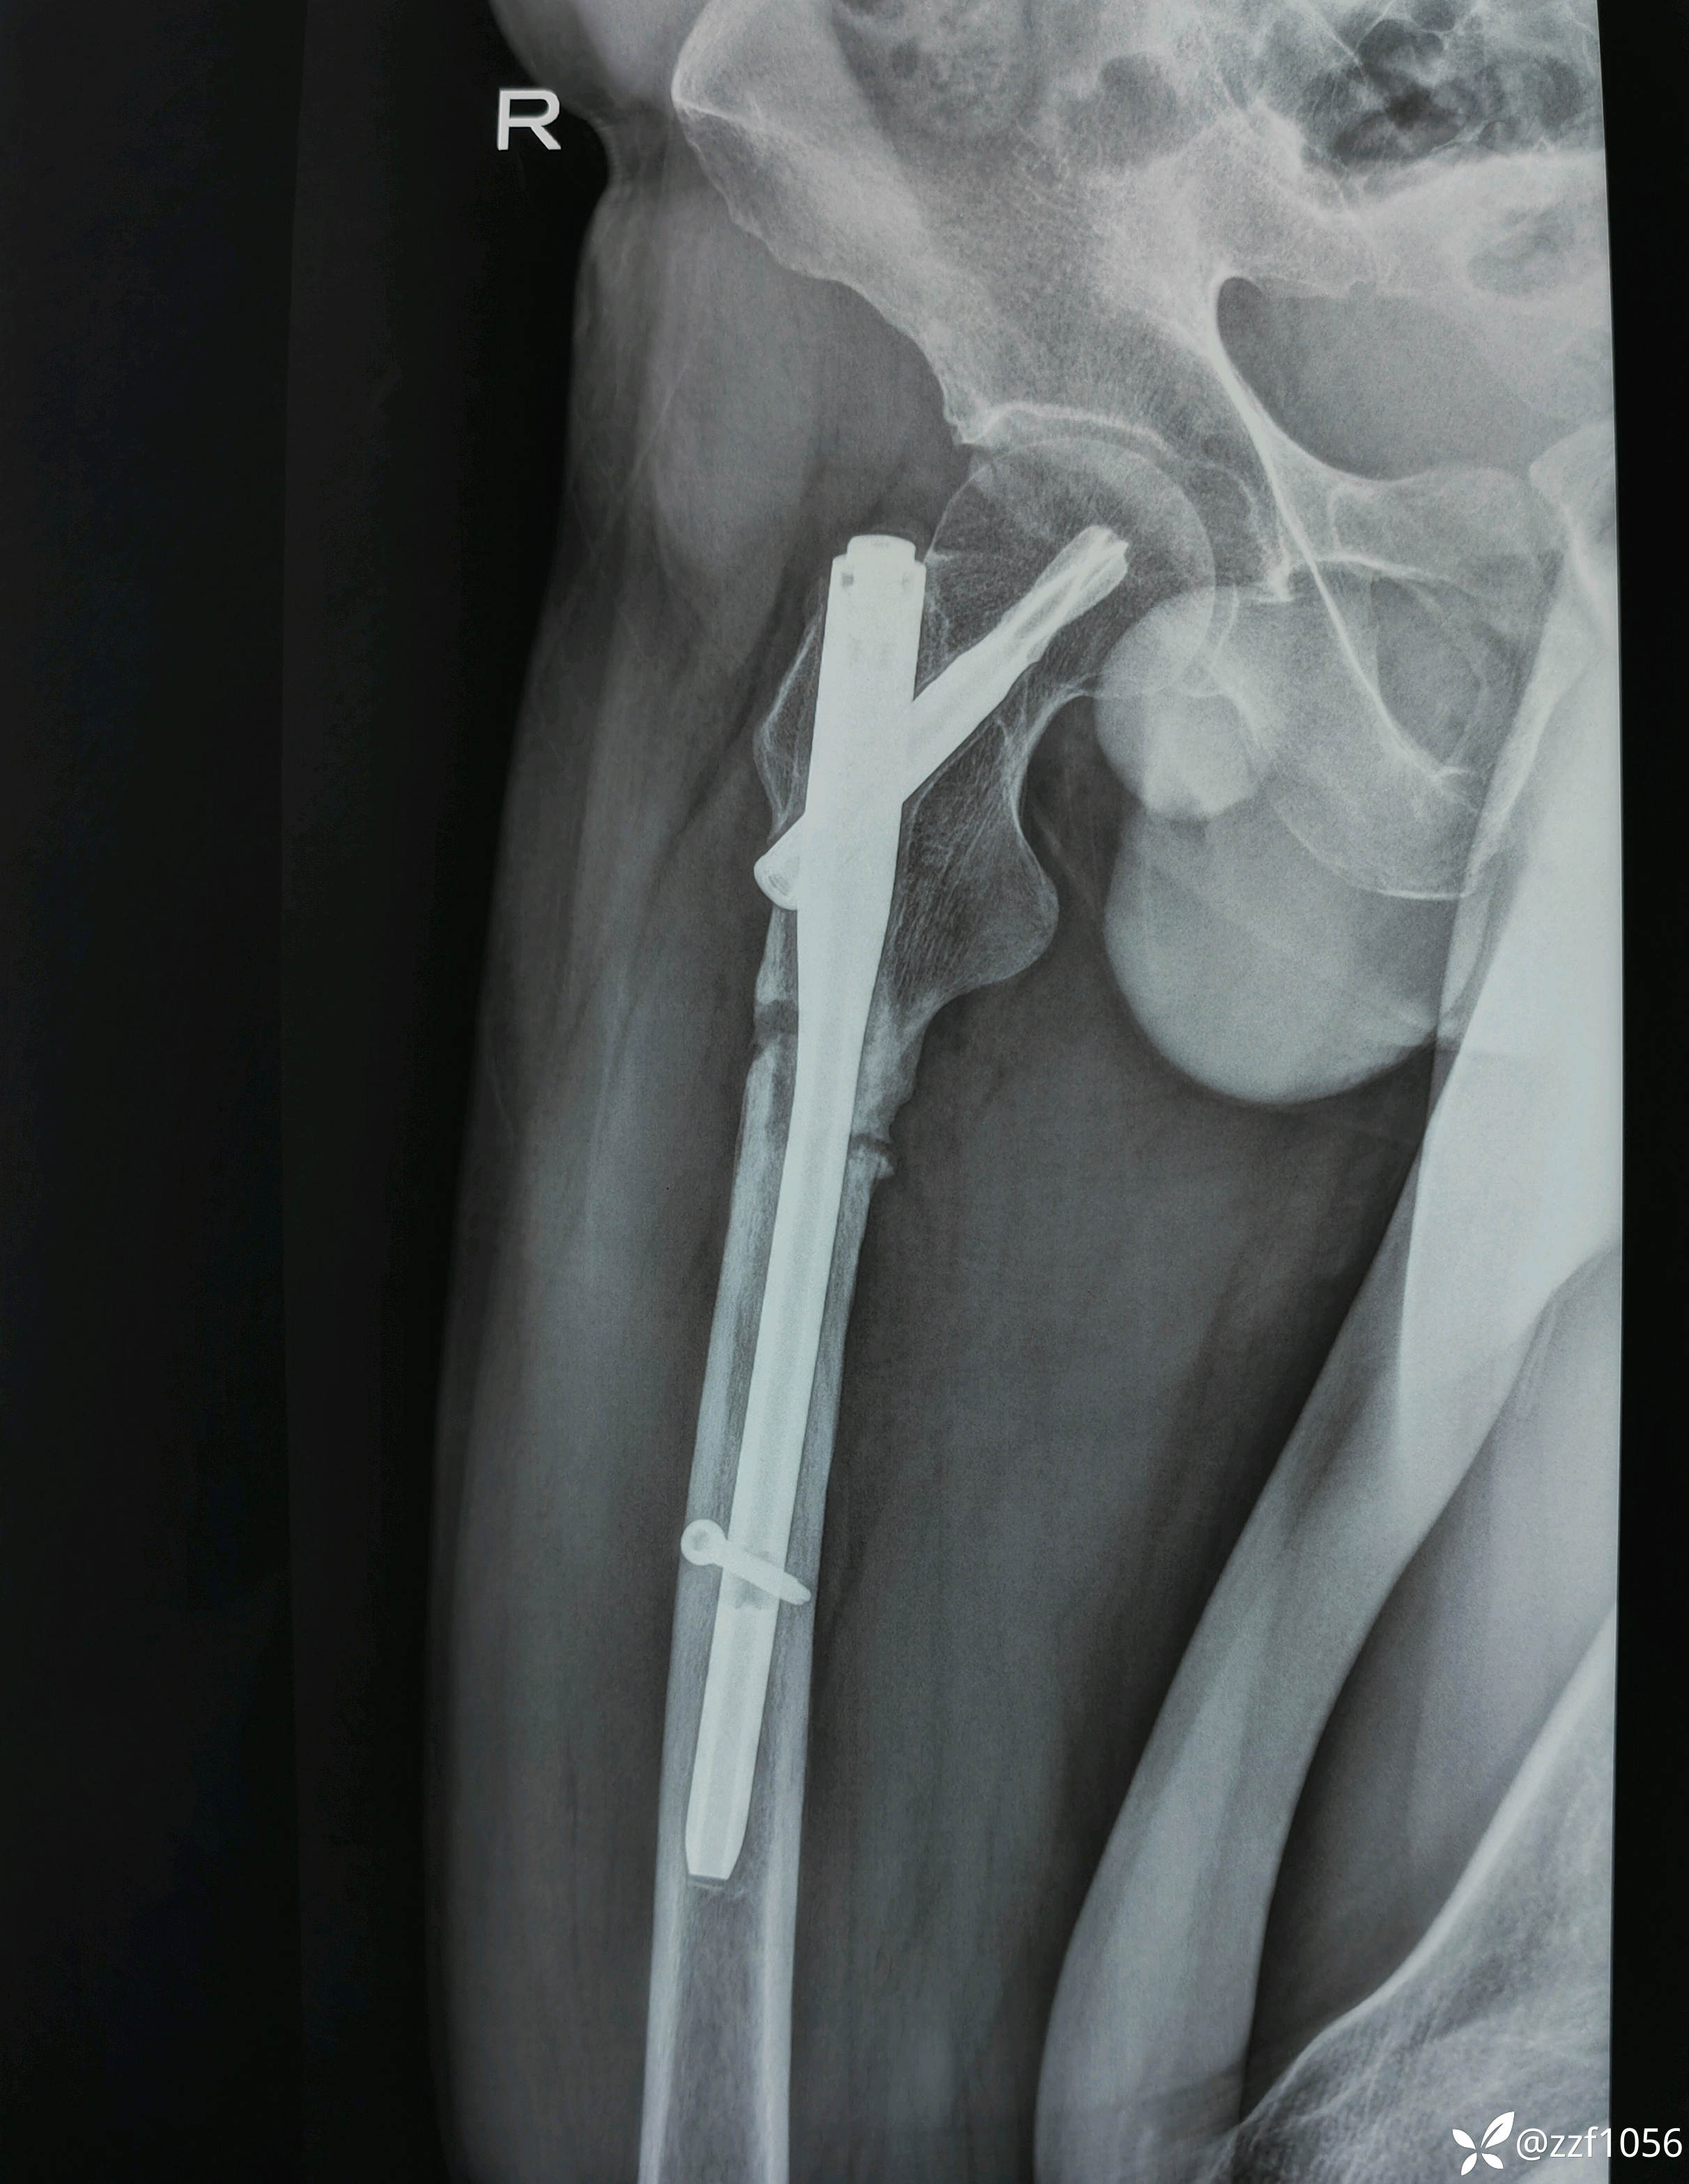

45岁转子下骨折PFNA术后一年骨不连

患者男性,45岁,右大腿骨折术后一年就诊。

当时在外省某医院手术,术后连续性每隔两月复查,曾在我院复查两次,骨折端均无生长迹象。